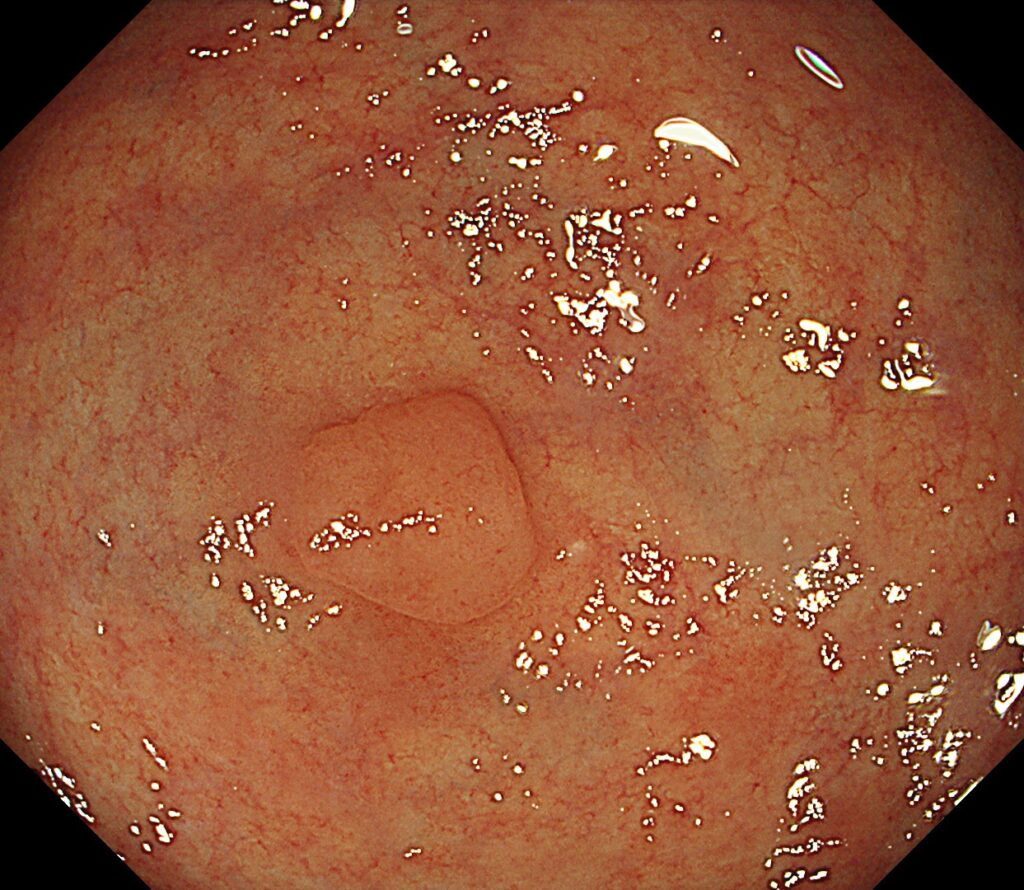

*生検にて腺腫と診断されて内視鏡治療を行った症例

腺腫性ポリープは、胃にできるポリープの中で最も注意が必要なタイプです。

胃の粘膜を構成する上皮細胞が異常増殖し、腺腫(せんしゅ)と呼ばれる「前がん病変」の状態になります。

つまり、良性と悪性の中間にあたる位置づけで、放置すると将来的に胃がんに進行する可能性があるのです。

このポリープは、組織検査(生検)で「異型腺腫」と診断された場合には、基本的に切除が必要です。

特に、大きさが5mm以上、表面が赤い・不整・びらんがあるといった特徴を持つ場合、がん化リスクが高くなります。

治療は、内視鏡を用いた内視鏡的粘膜切除術(EMR)または内視鏡的粘膜下層剥離術(ESD)が標準的です。

これらの手技は、胃カメラを使ってポリープを電気スネアで安全に切除する方法で、体への負担が少なく、早期がんの予防・治療にも効果的です。

腺腫性ポリープは見た目だけでは他の良性ポリープと区別がつかないため、必ず生検による確定診断が必要です。

検査で異型性が確認された場合は、がん化予防の観点からも早めの切除が推奨されます。

生検検査では腺腫であったが、内視鏡治療してみたら早期がんであったということは少なくありません。